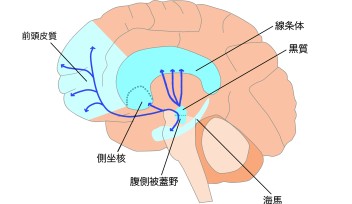

In the brain, dopamine helps regulate reward and body movement. As part of the reward pathway, dopamine is produced by neurons in the ventral tegmental area (VTA) and released in the nucleus accumbens and the prefrontal cortex, leading to the feeling of pleasure. Dopamine’s role in motor functions is linked to a separate pathway: first dopamine is produced in the substantia nigra and then it’s released in the striatum. While dopamine plays the same function in each case, malfunctions in the different pathways can cause vastly different diseases such as Parkinson’s and potentially schizophrenia.